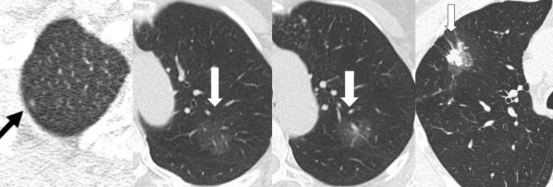

依据结节密度分类,肺部亚厘米结节可分为纯磨玻璃结节、部分磨玻璃结节和实性结节。

实性结节表现为均匀的软组织密度且其内血管和支气管影像被掩盖,部分磨玻璃结节介于两者之间。

不典型腺瘤样增生→原位腺癌

这两种病理类型属于肺腺癌浸润前病变,术前一般表现为纯磨玻璃结节,可以定期随访,一旦有变化,再行手术切除即可。由于病变的范围局限,手术方式一般选择亚肺叶切除即可,术后不会复发或者转移。5年生存率100%。

微浸润性腺癌

病理以贴壁生长方式为主,浸润范围较局限(<5mm),根据病变位置,楔形切除或者肺段切除即可,术后不会复发或者转移,5年生存率100%。